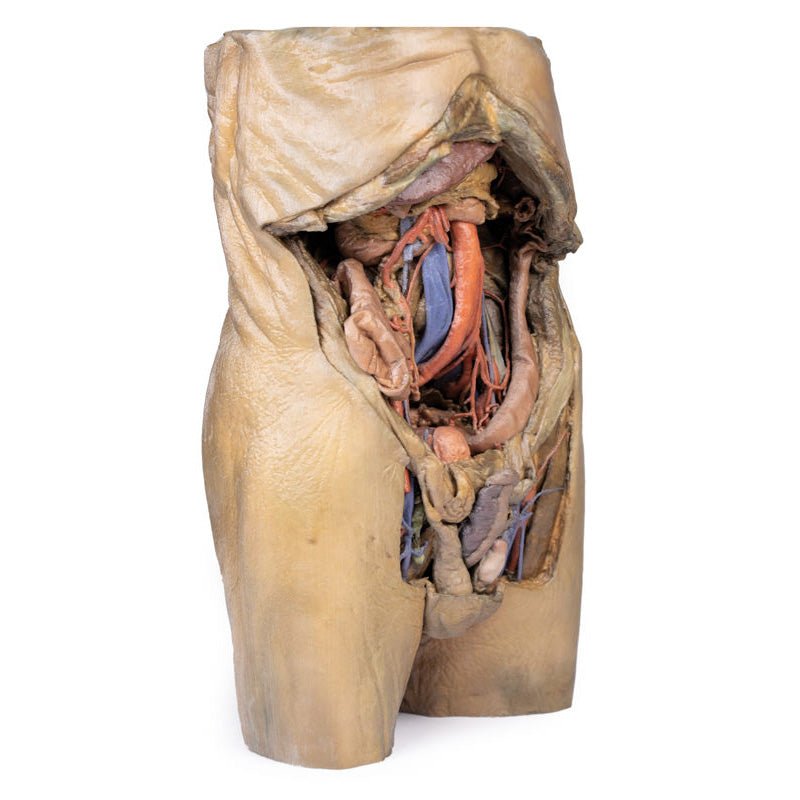

This 3D model represents one of the largest and most complex in the series, consisting of a partial torso from the diaphragm to the proximal thigh with a complete abdominal cavity preserving varying levels of dissection. This 3D model also records the rare, simultaneous occurrence of indirect and direct inguinal hernias allowing for a consideration of the anatomical underpinnings for both conditions. Given the scale of the dissection this 3D model description is divided into discrete parts based on views and regions.

The inguinal region and perineum

A distinctive and unique feature of this model is the dissection of

simultaneous direct and indirect hernias preserved on the right and left sides, respectively. While most of the

anterior abdominal wall has bee removed, the inferior epigastric arteries (and accompanying veins) have been

retained to allow for interpretation of the herniations. On the right side, a distinct outpouching of the

parietal peritoneum has formed medial relative to the inferior epigastric artery, representing an indirect

herniation event. On the left side, the hernia sac extends laterally relative to the inferior epigastric artery

and into the opened spermatic cord, with continuity of the epiploic appendage from the sigmoid colon into the

The skin over the perineum has been removed in order to demonstrate both the structure of the penis

(with both the corpus spongiosum and corpora cavernosa contrasted) and the position of the testes and spermatic

cords relative to the anterior abdominal wall. On the right side, which in this individual is impacted by a

direct hernia, the spermatic cord has been left undissected allowing for an appreciation of the external

spermatic fascia from the inguinal region through to the testis. On the left side, the spermatic cord has been

opened and is dominated by the enlarged and varicose testicular vein (reflecting the impact of the indirect

hernia exposed within the cord) just superior to the epididymis and exposed tunica albuginea of the testis.